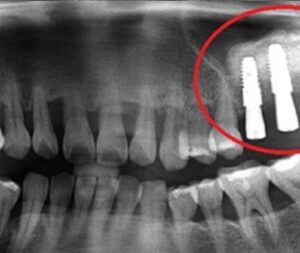

목동치과 🦷구치부 전악 임플란트 사례🦷

목동치과 🦷구치부 전악 임플란트 사례🦷   연세고운미소치과 목동점은 ‘고운미소치과 네트워크’1호점으로 2002년부터 양천구 목동에서 자리를 지켜왔습니다. · 치의학 박사 문원규 원장님 직접 진료 · 자연치아 보존한 후 최소 식립 · 치쥐료 후 건강한 잇몸에 식립 · 교정과 협진으로 식립 개수를 줄이는 노하우 · 임플란트 보증 사후 관리 시스템 과잉진료 없는 정밀한 더보기…

오목교역치과 🦷임플란트 시술 사례🦷

오목교역치과 🦷임플란트 시술 사례🦷   연세고운미소치과 목동점은 ‘고운미소치과 네트워크’1호점으로 2002년부터 양천구 목동에서 자리를 지켜왔습니다. · 치의학 박사 문원규 원장님 직접 진료 · 자연치아 보존한 후 최소 식립 · 치쥐료 후 건강한 잇몸에 식립 · 교정과 협진으로 식립 개수를 줄이는 노하우 · 임플란트 보증 사후 관리 시스템 과잉진료 없는 정밀한 검진, 더보기…